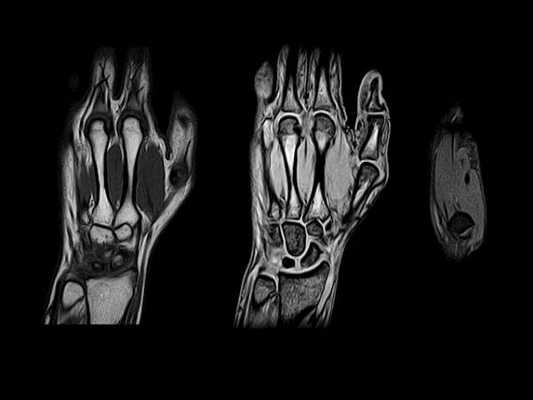

МРТ кисти в продольной проекции в норме

Артерии кисти при рентгенангиографии. В данном случае цифровая субтракционная ангиография не использовалась, что позволило продемонстрировать ход артерий относительно подлежащих костей. На первой из серии фронтальных Т1 МР-томограмм левой кисти показаны поверхностные ладонные структуры. На фронтальной Т1 МР-томограмме левой кисти показаны более глубокие ладонные структуры. На этом уровне можно обнаружить отделы пястно-фаланговых ладонных пластинок II-V пальцев (здесь отмечена пластинка только III пальца). Удостовериться, что это ладонные пластинки можно по их расположению и толщине. Обратите внимание, насколько они толще сухожилий сгибателей. На первой из серии фронтальных Т1 МР-томограмм правой кисти показаны поверхностные ладонные структуры. На фронтальной Т1 МР-томограмме правой кисти показаны более глубокие ладонные структуры. На этом уровне можно обнаружить отделы пястно-фаланговых ладонных пластинок II-V пальцев (здесь отмечена пластинка только III пальца). Удостовериться, что это ладонные пластинки можно по их расположению и толщине. Обратите внимание, насколько они толще сухожилий сгибателей. На фронтальной Т1 МР-томограмме левой кисти показаны пястные кости. Хотя в этой плоскости визуализируются преимущественно тыльные межкостные мышцы, можно увидеть часть 1-й ладонной межкостной мышцы во втором межпястном промежутке. О том, что это ладонная межкостная мышца свидетельствует то, что она отдает волокна от своего мышечно-сухожильного перехода к локтевому латеральному пучку II пальца, а не к лучевому латеральному пучку III пальца (в отличие от 2-й тыльной межкостной мышцы). На фронтальной Т1 МР-томограмме левой кисти (тыл) показаны несколько сухожилий общего разгибателя пальцев, а также сухожилие разгибателя указательного пальца. Обратите внимание на то, что коллатеральные связки ПМФ суставов, а также ДМФ суставов (здесь не показаны) не начинаются от латеральных вырезок головок фаланг в отличие от связок в пястно-фаланговых суставах (отходящих от боковых вырезок головок пястных костей). На фронтальной Т1 МР-томограмме правой кисти показаны пястные кости. Хотя в этой плоскости визуализируются преимущественно тыльные межкостные мышцы, можно увидеть часть 1-й ладонной межкостной мышцы во втором межпястном промежутке. О том, что это ладонная межкостная мышца свидетельствует то, что она отдает волокна от своего мышечно-сухожильного перехода к локтевому латеральному пучку II пальца, а не к лучевому латеральному пучку III пальца (в отличие от 2-й тыльной межкостной мышцы). На фронтальной Т1 МР-томограмме правой кисти (тыл) показаны несколько сухожилий общего разгибателя пальцев, а также сухожилие разгибателя указательного пальца. Обратите внимание на то, что коллатеральные связки ПМФ суставов, а также ДМФ суставов (здесь не показаны) не начинаются от латеральных вырезок головок фаланг в отличие от связок в пястно-фаланговых суставах (отходящих от боковых вырезок головок пястных костей).